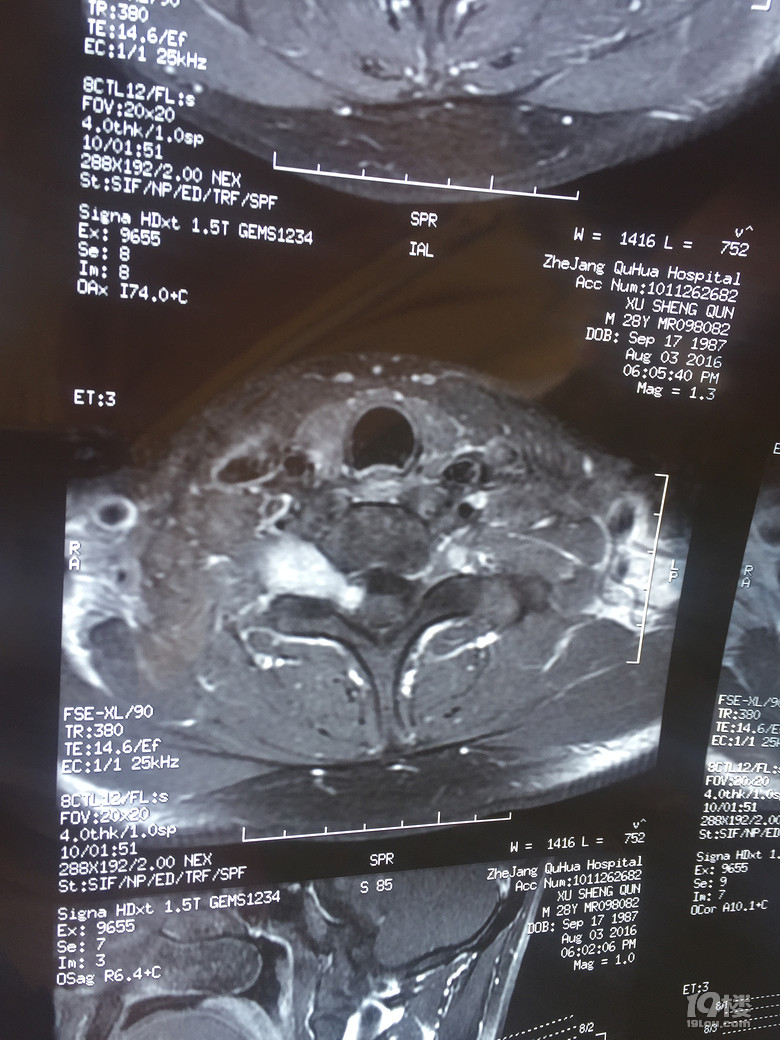

我要动手术了,求推荐【浙二医院脊柱肿瘤科】

我要动手术了,求推荐【浙二医院脊柱肿瘤科】

我要动手术了,求推荐【浙二医院脊柱肿瘤科】